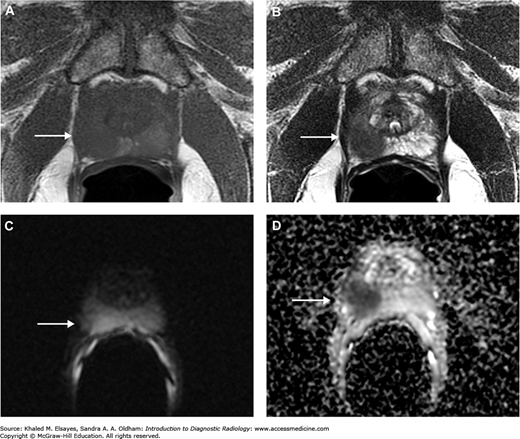

MRI with endorectal coil of a patient with prostate cancer. (A) Axial T1WI. (B) Axial T2WI. (C) DWI. (D) ADC map reveals a well-defined focal lesion exhibiting an isointense signal on T1WI and hypointense on T2WI, with restricted diffusion (arrow).